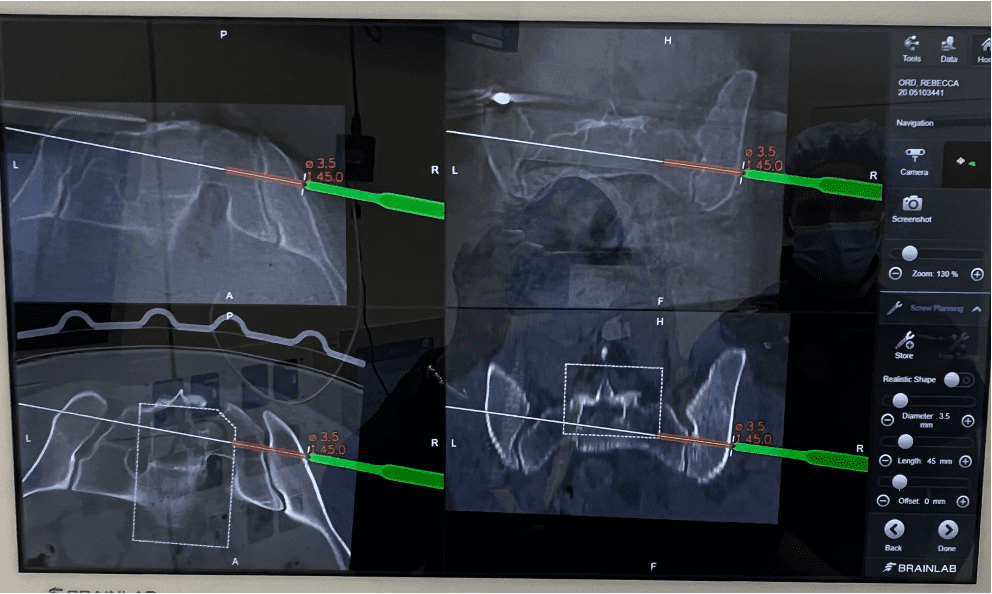

Diagnosing SI joint dysfunction can be challenging because its symptoms often mimic those of herniated discs or hip problems. A/Prof Buckland will take a detailed medical history, perform a physical examination, and use imaging tests such as X-rays, CT scans, or MRIs. In some cases, an injection of a local anesthetic into the SI joint under CT guidance is used to confirm the diagnosis.

• Surgery: In severe cases, minimally invasive SI joint fusion may be performed when conservative treatments fail. Learn more about SI Joint Fusion results.